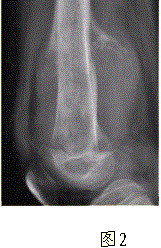

问题 患者男,16岁,左大腿下部疼痛伴肿胀2个月,逐渐加重。自感左膝上方胀痛,尤以夜间为著,伴行走困难。既往史及家族史无特殊。查体:左大腿下部明显肿胀,皮温较对侧升高。碱性磷酸酶明显增高。股骨平片及MRI见下图。 你认为对定性诊断有价值的征象是

选项 A.病变边缘模糊,内部信号不均 B.病变边缘骨皮质完整 C.病变周围可见软组织肿块 D.病变边缘可见骨膜反应,Codman三角形成 E.MR示病变周围骨髓明显水肿 F.病变内未见钙化影

答案 ACDEF